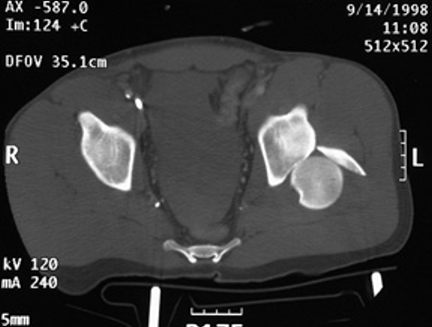

骨折與創傷8 / 9

【112-1 醫學(五) 第73題】20歲男性病人因車禍左髖關節腫痛。圖為本次就診之左髖關節X光攝影及電腦斷層影像。最可能的診斷為何?